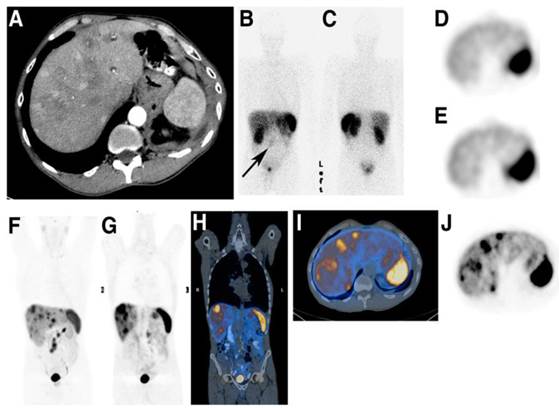

Somatostatin receptor imaging

The expression of SSTRs has been found in neuroendocrine tumours, small cell lung cancer, renal cell carcinoma, malignant lymphoma, breast cancer, and prostate cancer. PET-CT using somatostatin ligand analogues labelled with 68Ga has become a new golden standard in imaging of NETs with specificity and sensitivity well above 90% and advantages over conventional radiologic and scintigraphic imaging [14, 146-149]. It is the most pronounced example of theranostics [6, 7, 150].

Extensive basic research has been conducted on the development and biological validation of analogues varied in peptide sequence, size and number of peptide rings, chelator (DFO, DTPA, DOTA, NOTA, and their derivatives) and radiometal (Ga, Y, Tc, In, Lu) type. Their receptor binding affinity, internalization and biodistribution have been shown to be dependent on the chemical modifications [2]. Fast tumour localization, blood clearance, and renal excretion are typical characteristics of clinically used [68Ga]Ga-DOTA-TATE, [68Ga]Ga-DOTA-TOC, [68Ga]Ga-DOTA-1-Nal3-octreotide ([68Ga]Ga-DOTA-NOC). Structure activity relation studies allowed fine tuning for the agent properties such as receptor affinity, in vivo stability, biodistribution, pharmacokinetics, excretion pathway, and kidney uptake, and pharmacological activity [138, 151-155].

[68Ga]Ga-DOTA-TOC (27), [68Ga]Ga-DOTA-TATE (28) and [68Ga]Ga-DOTA-NOC (29) (Figure 6) are the most commonly used analogues in clinical studies [2, 166, 167]. Their pharmacokinetics, blood clearance and target localization rate are compatible with half-life of 68Ga. Renal excretion, short scanning time, high sensitivity and resolution assure high contrast and quality images over organs of interest as well as accurate quantitation. Relatively low radiation dose is one more advantage that should be mentioned. They served for diagnosis, staging, prognosis, therapy selection and response monitoring of NETs and other types of cancers and diseases. [68Ga]Ga-DOTA-TATE was compared with [68Ga]Ga-DOTA-NOC in 20 patients in terms of detection rate and SUVs [168]. The agents had comparable diagnostic accuracy with higher SUVmax for the former. One more analogue, [68Ga]Ga-DOTA-2-Nal, Tyr3, ThrNH28-octreotide (DOTA-lanreotide, DOTA-LAN) was successfully used for lung and thyroid tumour detection [169].

The individualized diagnosis has been practiced in the selection of patients for PRRT, target definition for fractionated stereotactic radiotherapy (FSRT) planning, target volume delineation for intensity modulated radiotherapy [170-174]. The diagnosis on the cellular and molecular level and determination of the disease associated biomarkers provides basis for the treatment optimization and efficacy for a particular patient [175]. The personalized therapy planning necessity was demonstrated in retrospective study of ten patients examined with [68Ga]Ga-DOTA-TATE [176]. It was concluded that the radiotherapeutical dose should be determined by the tumour burden since the latter influences the radioactivity distribution to the healthy organs, and in particular the higher burden decreases the radiation accumulation in the kidney. The starting point of PRRT after preceding cold octreotide therapy in patients with NETs could be determined [177]. These imaging agents improved the detection rate and diagnostic accuracy [178, 179]. They were used for therapy planning and monitoring response to treatment [180], as well as influenced and changed the therapeutic course [181-184].